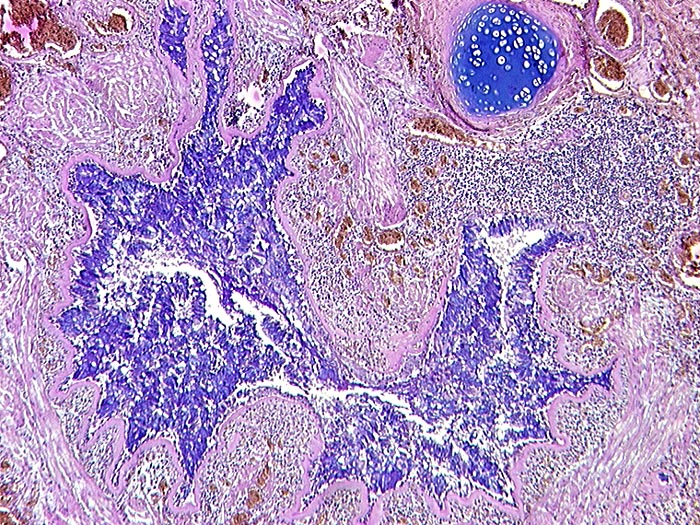

Asthma bronchiale

Kleiner Bronchus mit Becherzellhyperplasie, starker Verdickung der Basalmembran und Hypertrophie der glatten Muskulatur. Sternförmiges Lumen.

Tod im Asthmaanfall bei bekanntem Asthma bronchiale.